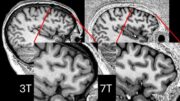

Neue MRT-Technik ermöglicht sicherere Epilepsie-Chirurgie

7T–Ultrahochfeld-MRT-Scanner ermöglichen bei Gehirnscans eine deutlich detailliertere Auflösung als 3T-MRT-Scanner, allerdings sind sie auch anfällig für dunkle Flecken, die als Signalausfälle bekannt sind. Dieses Problem haben Forschenden nun mithilfe einer Technik gelöst, die als „paralleles Senden“ (pTx) bekannt ist und bei der sie acht Elemente eines Spulen-Arrays verwendeten, um die problematischen Aussetzer zu vermeiden.